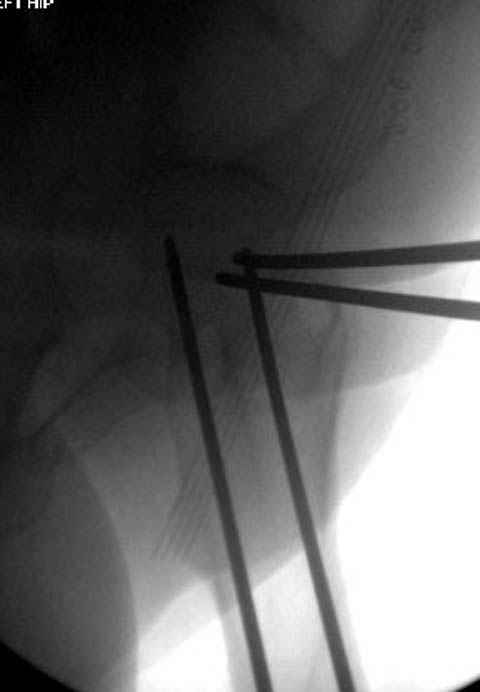

Уважаемые коллеги! С прошедшеми Вас праздниками. Теперь ближе к трудовым будням. Поступила 16 летняя девушка неделю назад. Механизм травмы падение с 5 этажа. Краткий диагноз:закрытый перелом левой ключицы, левого плеча, закрытый вертикально и ротационно нестабильный перелом костей таза:закрытый перелом левой подвздошной кости, переломы лонной кости справа, перелом обоих колонн вертлужной впадины слева;субкапитальный перелом шейки левой бедренной кости со смещением. По тактике лечения таза возникли следующие вопросы: 1. С чего начать - фиксации переломов вертлужной впадины или устранения деформаций таза? 2. Надо ли фиксировать шейку или фиксировать бедро в аппарате вместе с тазом, а после сращения таза планировать ТЭП ТБС? Если имеются еще какие подводные камни, будем рады выслушать.Спасибо.

Долгое ожидание повышает риск АВН головки,

рекомендуется ургентная фиксация шейки в первые сутки, а в дальнейшем таз.

В данный момент скелетное вытяжение поучается через перелом шейки, а фиксированный перелом шейки будет участвовать в процессе вытяжения через каннюлированные шурупы.

Фиксацию шейки провели когда получили окно, быстро

перкутанно смогли провести шурупы.

В положении на спине подвздошным и надлобковым доступом восстанавливается тазовое кольцо, фиксация пластинами. При хорошей репозиции может улучшиться конгруэнтность в суставе.

Затем, если положение хорошее, закрытый остеосинтез шейки винтами.

Если нет - в положении на боку, синтез задней колонны из наружно-латерального доступа и синтез головки винтами, но уже под визуальным контролем.